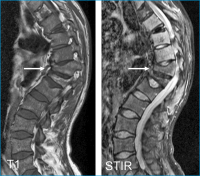

Wirbelkörperfraktur

Abbildung 3: MRI T1 und STIR Wirbelsäule: Wirbelkörperfrakturen Th11 und Th 12 mit Kyphoseknick (Pfeil). Verminderte Signale der Wirbelkörper in den T1- und STIRSequenzen typisch für ausgedehnte Markinfiltration bei Mb. Gaucher.